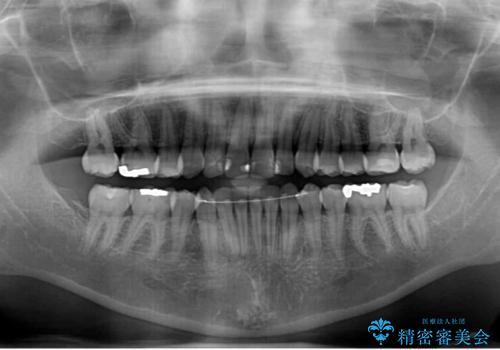

- 上下の八重歯を気にして来院された患者様です。

八重歯の後ろの歯を1歯抜歯し、補助装置(リンガルアーチ)を用いて八重歯の位置を改善し、その後インビザラインにより矯正治療を行うこととしました。

右側のみ上下小臼歯を抜歯したため、上下の正中が右にずれてしまう可能性があります。

また、元々右側は上下が咬み合っていないため、矯正をしても咬み合わないことも考えられました。

治療期間はかかりましたが、正中も合い、綺麗な仕上がりとなりました。